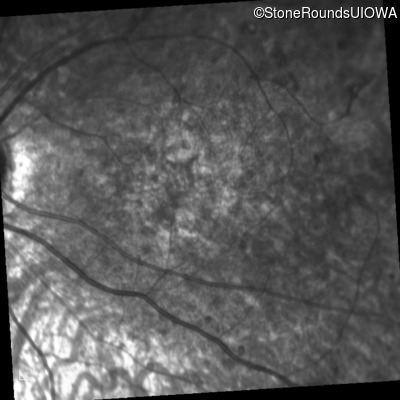

Infrared Fundus Photograph - Right - 5/200

Exemplar